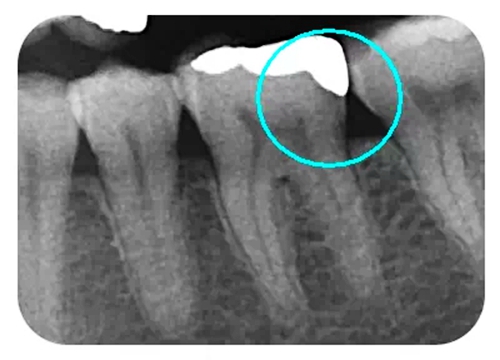

從下面這張X線中可以看出,嵌體遠中邊緣沒有懸突,與牙體邊緣密合相接。